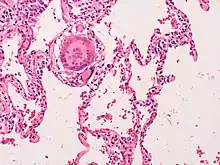

Histological samples of lung tissue with pneumonitis include the presence of poorly formed granulomas or mononuclear cell infiltrates. The presence of bronchocentric lymphohistiocytic interstitial pneumonia with chronic bronchiolitis and non-necrotising granulomas coincides with pneumonitis.[12]